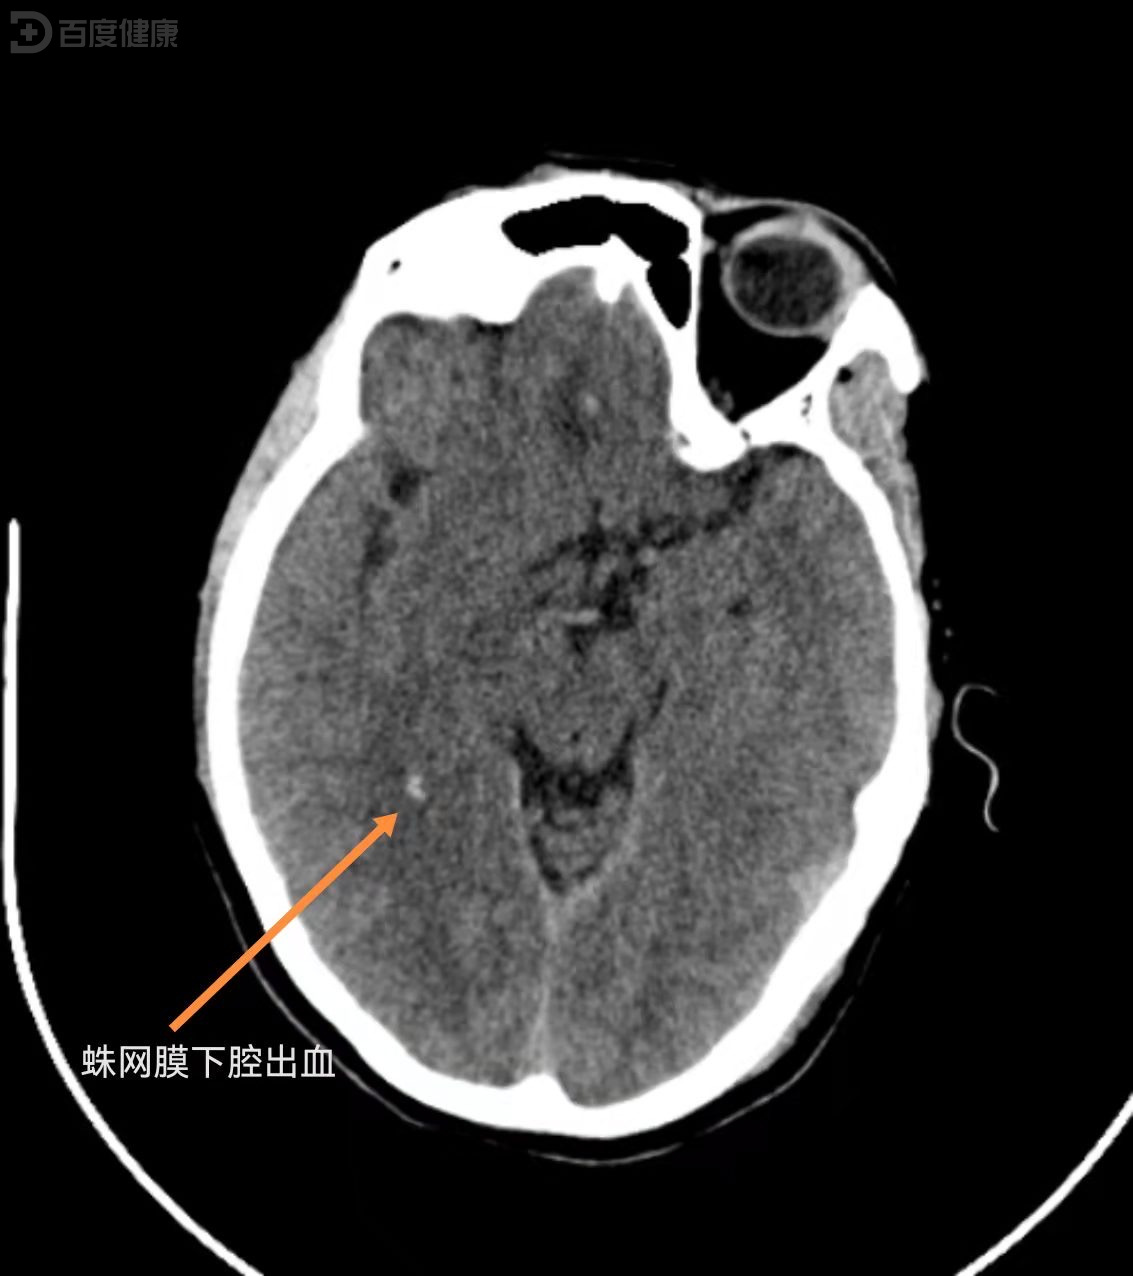

蛛网膜下腔出血是什么?

蛛网膜下腔出血是脑出血的一种特定类型以下是对其的详细解释定义与位置蛛网膜下腔出血指血液积聚于蛛网膜下腔的病理状态蛛网膜是包裹在大脑表面的一层透明薄膜,类似核桃内部的薄膜结构,其与软脑膜之间的腔隙即为蛛网膜下腔当血液进...